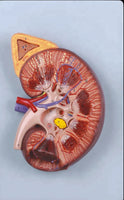

Modelo de Riñón maxizado con Glándula renal rinon

Modelo de Riñón maxizado con Glándula renal riñón

sistema urinario maximizado

Medidas del producto: 21 x 28 x 9 cm